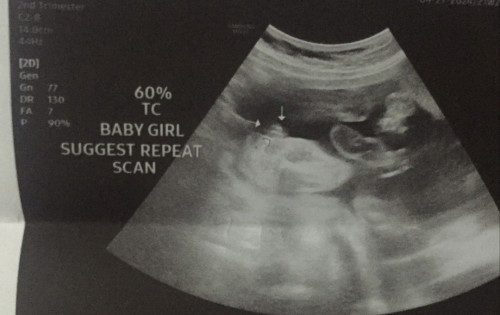

Wala daw kase signs na boy at 60% daw na girl hehe ano po sa tingin nyo?